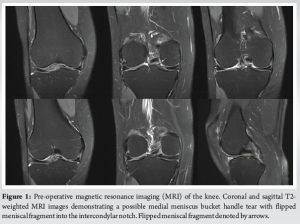

We present the case of a 38-year-old female who presented to the outpatient orthopedic clinic complaining of right knee pain. She had a past medical history of asthma, polycystic ovary syndrome, and anxiety, but no surgical history related to the knee. About 2 weeks before presentation, the patient experienced a sharp onset of knee pain after she knelt onto the affected knee. In addition to pain, the patient reported swelling, popping, and a locking sensation in the knee. She denied any prior trauma or injury to the knee, numbness, or tingling in either leg. She also denied any history of knee pain, popping, clicking, or catching before the kneeling event. On physical examination, there was a moderate effusion present and medial joint line tenderness as well as a positive medial McMurray test. Active and passive range of motion demonstrated one-degree loss of extension compared to the contralateral side. Her knee was stable to anterior, posterior, and varus/valgus stress. Patella examination was within normal limits. Magnetic resonance imaging (MRI) was performed and showed a medial meniscal fragment spanning from the posterior horn to the anterior horn within the intercondylar notch that was consistent with a flipped bucket handle tear (Fig. 1).

Anomalies of the medial meniscus are uncommon compared to anomalies of the lateral meniscus, and they include discoid variants, hypoplasia of the anterior horn, and anomalous insertion of the anterior horn [13]. There have been limited case studies published involving anomalies of the posterior horn of the medial meniscus. One case describes a fibro-cartilaginous fold that covers the medial femoral condyle (but reports a normal posterior horn), and another case describes a fibrous band arising from the posterior horn, connecting it to the ACL [16,17]. Mariani et al. reported the first published case involving a combined anomaly of the posterior and anterior roots of the medial meniscus [13]. However, this case did not describe an anomalous connection between the horns, forming an “O” shape, and mimicking a bucket handle tear. Most reported anomalies of the medial meniscus involve insertion into the ACL, not the PCL. The overall prevalence of anomalous insertion of the medial meniscus into the ACL is 1.2–2.3%[18]. Due to the relatively high prevalence of this morphology, a classification system exists that breaks down anomalous insertion of the medial meniscus into the ACL. These three distinct subcategories are based on insertion location and include: Type 1 (into the lower portion), type 2 (into the middle portion), and type 3 (into the proximal portion; intercondylar notch), with type 2 being the most common [19]. A medial discoid meniscus was first described in 1941, about 50 years after a lateral discoid meniscus was first described by Tachibana in 1889 [20]. Since discoid menisci became a topic of research, it became abundantly clear that a lateral discoid meniscus is significantly more common than the rare medial discoid meniscus. In 10,000 meniscectomies performed by Smillie, 467 had a lateral discoid meniscus compared to just those that had a medial discoid meniscus[21]. Furthermore, in 14,731 menisci examined by Dickason et al., 10 of 8,040 (0.12%) medial menisci were discoid, whereas 102 of 6,691 (1.5%) lateral menisci were discoid [22]. Some controversy still exists regarding the pathogenesis of discoid menisci: Two predominant existing theories are Smillie’s embryological theory and Kaplan’s developmental and biomechanical hypothesis [23]. Smillie posited that a discoid meniscus is a result of an arrest in the normal development of the meniscus during embryogenesis [21,24]. Kaplan, on the other hand, proposed that abnormal mechanical forces during knee development could lead to the persistence of the discoid shape [25]. This hypothesis is supported by the observation that the lateral meniscus, which is more frequently affected by the discoid variant, covers a larger surface area of the tibial plateau during fetal development, making it more susceptible to abnormal mechanical stresses [24,25]. Given that medial discoid menisci are extremely rare, only small case series have been published in the literature. Our case, however, differs from all described anomalies in the literature as the meniscal band arising from the posterior horn of the medial meniscus connected to the anterior horn of the medial meniscus, thereby forming an “O” shape. A musculoskeletal 162 radiologist and fellowship-trained sports medicine orthopedic surgeon identified the pathology on MRI as a bucket-handle medial meniscus tear. There is literature that describes the MRI appearance of an anomalous insertion of the medial meniscus into the ACL, where there is a low signal intensity band that goes from the anterior horn of the medial meniscus, covering the ACL, and into the intercondylar notch [19,26]. That appearance, however, does not mimic that of a bucket-handle meniscus tear. The MRI appearance of our patient’s knee was likely complicated by the fact that there was an anomalous connection between the anterior and posterior roots of the medial meniscus, which appeared like a flipped meniscal fragment. An interesting aspect of this case was the lack of mechanical or painful symptoms present before the kneeling event, despite the anomalous meniscus still existing in the patient’s knee. It is very possible that this one event caused a mechanical disturbance of the anomalous tissue, displacing it into a position it was not in before the kneeling event, thereby causing new symptoms. However, it is not completely known why this one kneeling event precipitated symptoms. Finally, a large patellofemoral plica overlying the lateral femoral condyle was identified intraoperatively. This may have been an incidental finding but could have contributed as a source of pain. It also could have a potential association with the anomalous meniscus. However, there is no literature identifying an association between an anomalous medial meniscus and patellofemoral plica. Further investigation into this possible association is warranted.